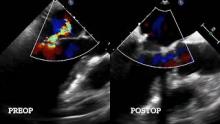

After coming off bypass, a transesophageal echocardiography showed postoperative results with mild mitral central regurgitation and no significant valve stenosis (mean gradient 5mmHg, maximum gradient 8mmHg). The patient was discharged uneventfully four days after surgery.

Seven months after surgery, the patient was doing well. The echocardiography showed an effective mitral valve repair without mitral regurgitation or stenosis (gradients were stable, EF 50%).